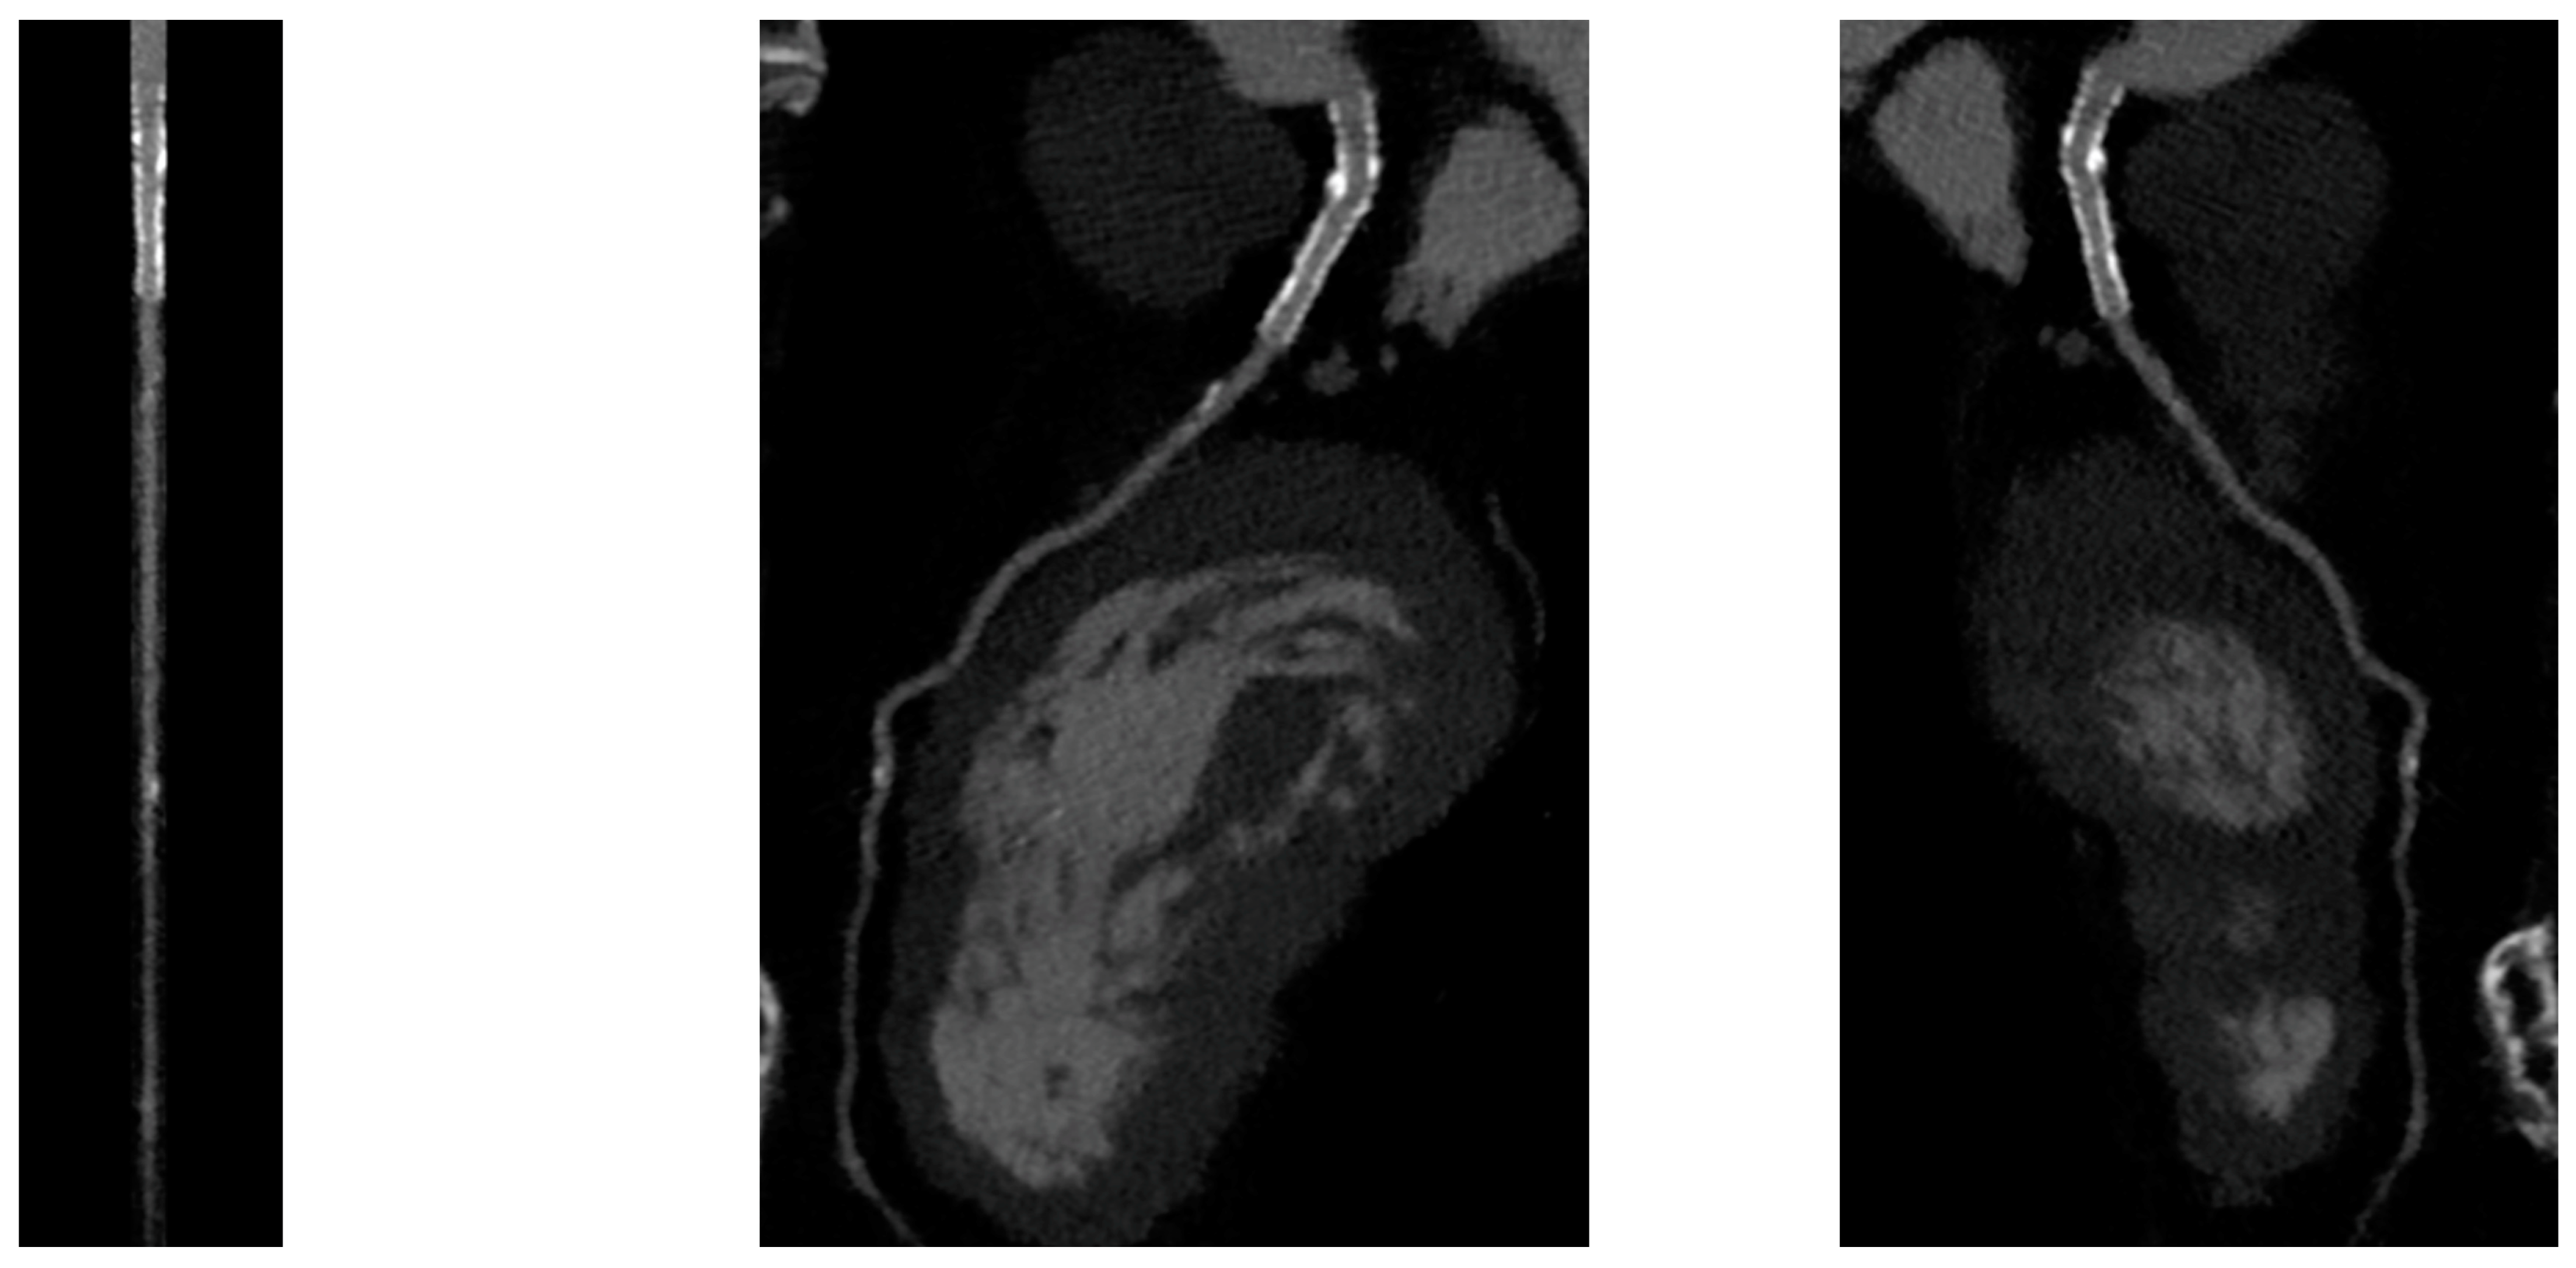

Figure 3.

CCTA assessment of BRS. Orange brackets highlight the two markers of BRSs whose struts result in complete reabsorption. The vessel is also well analyzed in the scaffolded segment.

Figure 4.

Anatomical and functional assessment of ISR in a scaffold (orange bracket). ISR appears to be characterized by a major calcific part, and the stenosis results were significant under the FFR-CT assessment. FFR-CT was performed with DeepVessel FFR (DVFFR) software (Keya Medical, Seattle, WA, USA).